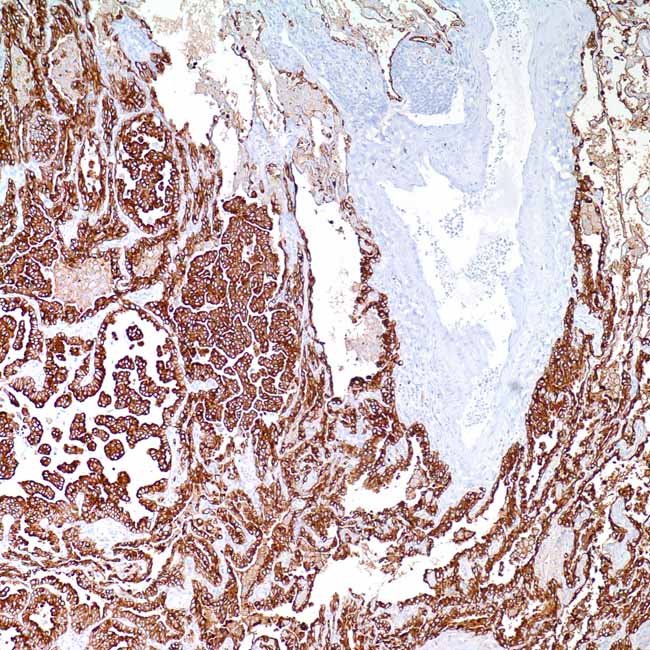

Cytokeratin 7 (OV-TL 12/30)

Cytokeratin 7 (CK7) labeling can aid in differentiating between lung,1 breast, and urothelial cancers, which are typically positive, and colon and prostate cancers, which are often devoid of CK7 expression.2-7 CK7 is a frequent marker for primary lung adenocarcinomas and is also seen in other primary lung carcinomas and non-pulmonary carcinomas.1 Furthermore, anti-cytokeratin 7 has proven helpful in the differential diagnosis of ovarian malignancies.8 Anti-cytokeratin 7 interacts with proteins that are present in the majority of epithelial cells in the biliary duct, ductal, glandular, and transitional tissues.

ControlLung adenocarcinoma (Cytoplasmic); Salivary gland (Cytoplasmic)